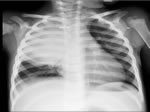

Al 7° giorno le condizioni cliniche e l'obiettività toracica di Sara erano un pò migliorate, ma era sempre presente febbre (39-40°C); la PCR era in ulteriore calo: 2,5 (Figura 2).

Focolaio BPN dx che interessa il lobo superiore e medio, con piccola falda di versamento Figura 2

Ripete la Radiografia del torace che evidenzia in sede centrale al focolaio un'area di pneumatizzazione (Figura 3).

ingrandisci (63 Kb) Andamento della febbre (in rosso), antibiotici utilizzati, valori della PCR Figura 3